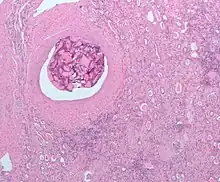

L'embolisation est un procédé thérapeutique consistant en l'occlusion sélective de vaisseaux sanguins par l'injection d'un agent embolique. Elle est utilisée dans le traitement d'une large variété de pathologies et est généralement réalisée par un radiologue interventionnel.

Les tumeurs hépatiques peuvent aussi bénéficier de cette modalité thérapeutique et il est même possible de réaliser dans ce cas une chimio-embolisation intra-artérielle. L'occlusion des artères nourricières par l'agent embolique est alors associée à l'injection intra-tumorale d'une chimiothérapie.